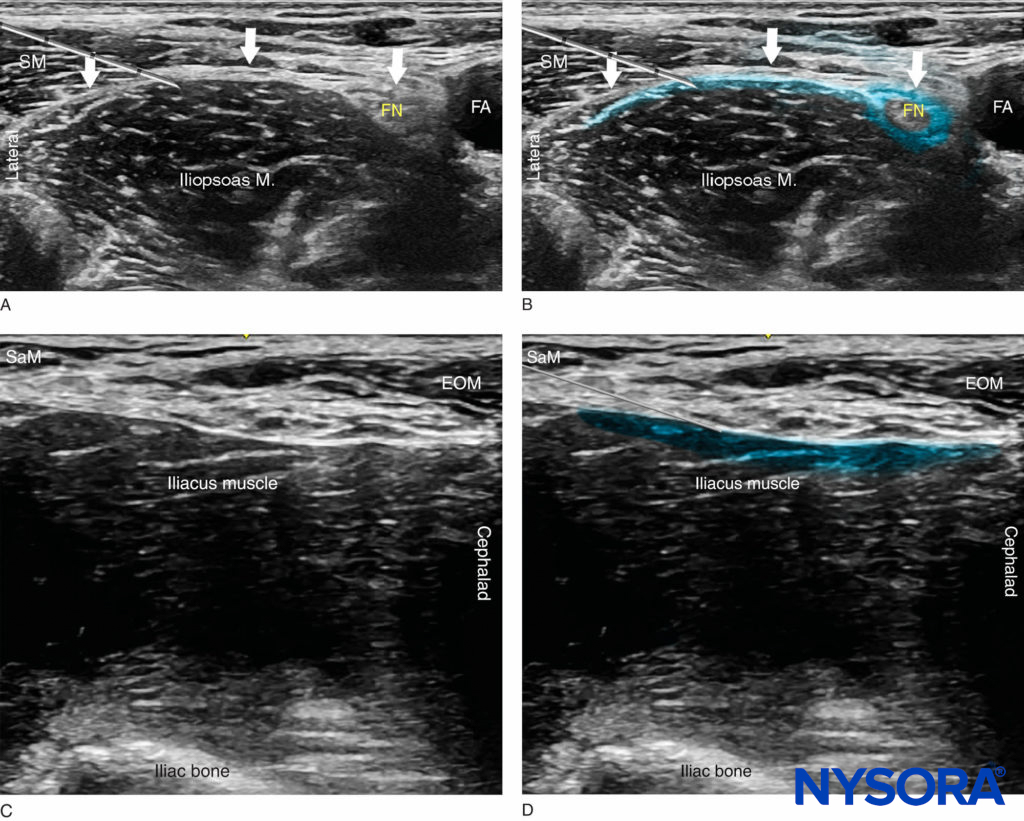

FIGURE 4. Ultrasound image of the fascia iliaca (white line and arrows) at the level of the inguinal ligament. The femoral nerve (FN) and femoral artery (FA) are visualized on the medial side and the sartorious muscle (SM) on the lateral side.

As the needle eventually pierces the fascia, a “pop” may be felt, and the fascia may be seen to “snap” back on the US image. After negative aspiration, 1–2 mL of local anesthetic is injected to confirm the proper injection plane between the fascia and the iliopsoas muscle (Figure 5a, b).

Releasing the pressure of the transducer may reduce the resistance to injection and improve the distribution of local anesthetic. If the spread is deemed inadequate, additional injections laterally or medially to the original needle insertion or injection can be made to facilitate the medial–lateral spread. In an adult patient, 20–40 mL of local anesthetic is usually required for successful block. In children, 0.7 mL/kg is commonly used. The success of the nerve block is best predicted by documenting the spread of local anesthetic toward the femoral nerve medially and underneath the sartorius muscle laterally (Figure 5b). In obese patients, an out-of-plane technique may be favored.

FIGURE 5. (A) Position of the needle tip for the fascia iliaca nerve block. The needle is shown underneath the fascia iliaca lateral to the femoral artery but not deep enough to be lodged in the iliac muscle. (B) A simulated spread (blue-shaded area) of local anesthetic to accomplish a fascia iliaca nerve block. (C) Ultrasound view of the supra-inguinal approach with the probe oriented in a sagittal plane along the iliacus muscle. (D) Needle path and simulated local anesthetic spread (blue-shaded area) just deep to the fascia iliaca and the external oblique muscle (EOM). SaM, sartorius muscle.